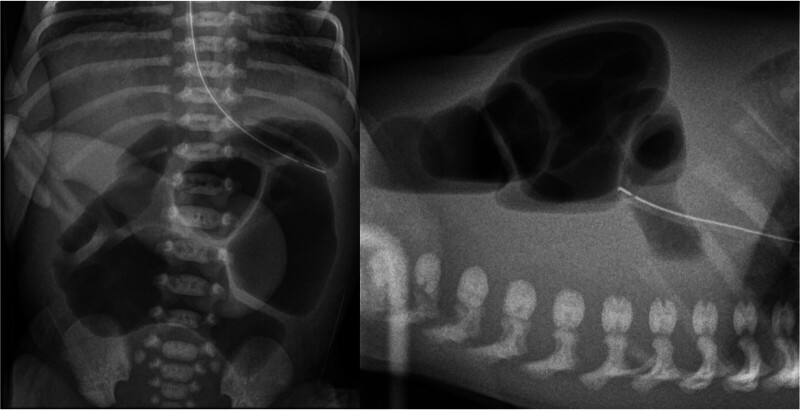

A newborn of 32 + 6 weeks' gestational age with prenatal diagnosis of gastroschisis was born through elective caesarean section. Ultrasonography at 16 + 4 gestational weeks (GW) showed a gastroschisis with free bowel loops floating in amniotic fluid. From 27 + 4 GW onward, serial ultrasounds showed the disappearance of extra-abdominal intestine and progressive intra-abdominal intestinal loops dilation, raising suspicion for vanishing gastroschisis. Birth weight was 2,136 grams and the external appearance of the abdomen was normal. An exploratory laparotomy was performed, finding a dilated proximal jejunal loop with a type III intestinal atresia, microcolon, and no other remainder bowel in between. The total length of the small intestine was 21 cm. Serial transverse enteroplasties for intestinal lengthening (reaching 38 cm), along with lateroterminal jejunocolic anastomosis were performed. The patient was discharged after 5 months of hospitalization with home parenteral nutrition. At 2 years and 8 months of age, the child is thriving and off parenteral support. Vanishing gastroschisis is a rare and severe form of complex gastroschisis whose prenatal diagnosis is crucial for parental counseling, timely delivery, and early surgical intervention. Multidisciplinary approach is essential to manage intestinal failure and improve long-term outcomes in these patients.

本文报道一胎龄32 + 6周,产前诊断为胃裂的新生儿通过选择性剖宫产出生。孕16 + 4周(GW)超声检查显示胃裂,游离肠袢漂浮在羊水中。从27 + 4gw开始,连续超声显示腹外肠消失,腹内肠袢进行性扩张,怀疑胃裂消失。出生体重2136克,腹部外观正常。进行剖腹探查,发现空肠近端袢扩张伴III型肠闭锁、微结肠,其间无其他剩余肠。小肠总长度为21 cm。连续行横向肠成形术延长肠长度(达38厘米),同时行侧端空肠结肠吻合。患者住院5个月后经家庭肠外营养治疗出院。在2岁零8个月大的时候,孩子正在茁壮成长,不需要外部支持。消失性胃裂是一种罕见且严重的复杂胃裂,其产前诊断对家长咨询、及时分娩和早期手术干预至关重要。多学科方法对于治疗肠衰竭和改善这些患者的长期预后至关重要。